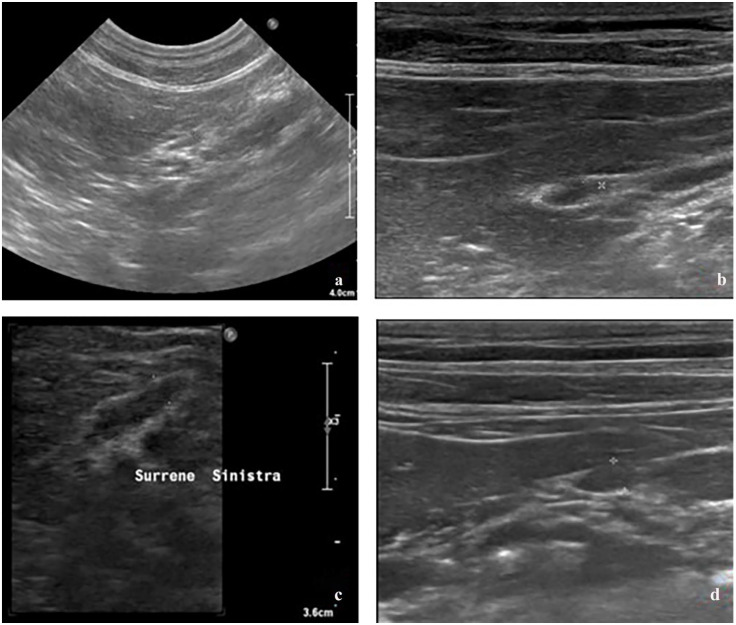

Case summary: A 12-year-old castrated male domestic shorthair cat was referred for investigation of lethargy, hindlimb weakness with plantigrade stance and ventroflexion of the neck. The cat was fed a balanced diet and had received methylprednisolone acetate at a dose of 20 mg intramuscularly every 6 months for 6 years. On blood work, severe hypokalaemia and marked elevation of muscle enzymes were noticeable. The findings were suggestive of hypokalaemic myopathy. Urine fractional excretion of potassium (FEk) was moderately high (9.04%), and serum aldosterone was below the reference interval. An adrenocorticotropic hormone (ACTH) stimulation test was compatible with adrenal suppression. Upon hospitalisation, the patient was given intravenous (IV) Ringer lactate solution supplemented with potassium chloride and oral potassium citrate. The serum potassium concentration normalised by the fifth day of hospitalisation; therefore, IV potassium supplementation was suspended. The cat was discharged with oral potassium and the dose was gradually reduced over time. After 4 months, the cat was clinically normal; the serum potassium concentration remained within the normal range and the adrenal glands showed some response to ACTH stimulation. Potassium supplementation was therefore discontinued. One month later, the serum potassium concentration was still within normal limits and at the time of writing (7 months after presentation), no clinical signs had reoccurred.

Relevance and novel information: This report describes a case of hypokalaemic myopathy associated with iatrogenic hypercorticism in a cat. This condition was successfully treated with supplementation of potassium and a complete clinical remission was achieved within 4 months.